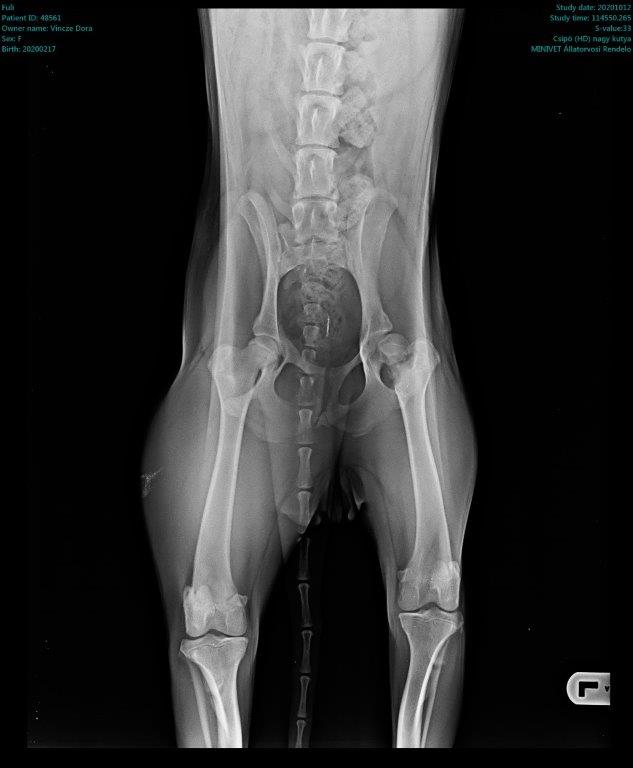

Füli kutyusunk egy jelenleg kb másfél éves, mentett, bántalmazott keverék, szuka kutyus (15 kg-os, vékony testalkatú, közepes magasságú, rövidszőrű keverék kutyus). Sérülése egy korábbi bántalmazásból eredt, mikor kiskutyaként husánggal úgy megverhették, hogy combnyaktörése lett. Ezt mi derítettük ki, mikor hozzánk került tavaly októberben. Akkor észrevettük, hogy aggasztóan sántít, és elvittük megröntgeneztetni. Több orvos véleményét is kikértem, és mindannyian azt tanácsolták, hogy műttessük meg (elég drasztikus műtéttel, a combcsontfej egy részét kivágták volna).

Molnár doktor úr egyedüliként, a röntgen kép alapján, arra bíztatott, hogy mivel a kutyus még növekedésének vége előtt állt, próbáljunk ki egy 3 hónapos csont- és porcépítő csomagot. Így is tettünk. Már kezdetben is nagy javulást észleltünk. Pár hét után el-elmaradozott a sántítás és szép lassan teljesen elmúlt. De természetesen nem elégedtünk meg ennyivel. Májusban az ivartalanítási műtét során kértem az orvost, hogy készítsen röntgenfelvételt Füli lábáról. A röntgen el is készült, és nagy örömünkre, már ez az állatorvos is azt mondta, hogy nincs szükség a combcsontfej műtétjére.